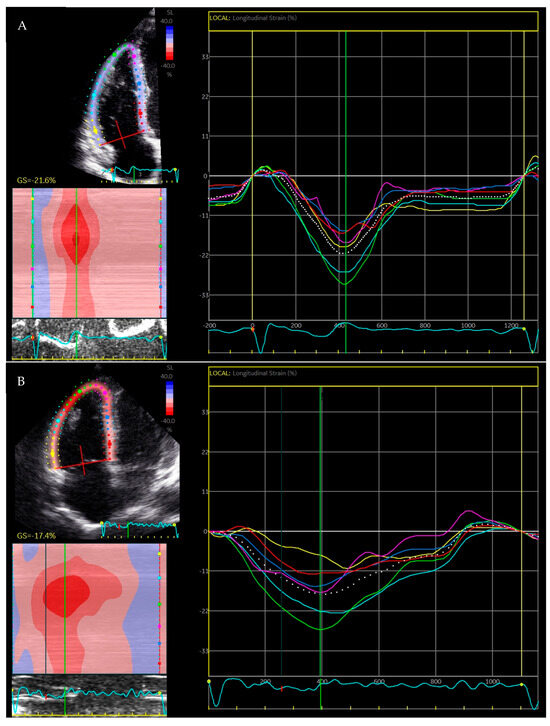

2.2. Right Ventricular Strain

3.2. Regional Strain

3.3. Mechanical Dispersion

4. Right Ventricular Strain and Ventricular Arrhythmia